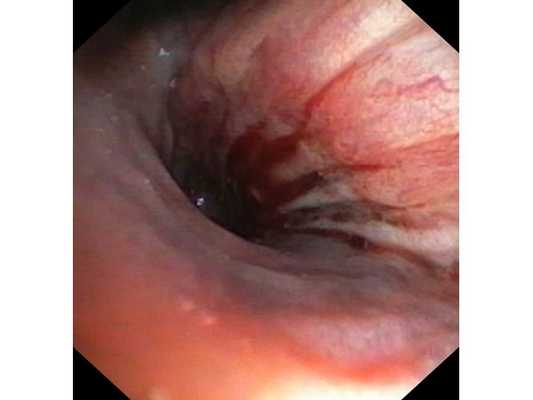

Первым этапом пациенту была проведена фибробронхоскопия, по данным которой выявлено, что устье нижнедолевого бронха слева сужено за счёт подслизистого и перибронхиального распространения опухоли.

Выполнена многократная биопсия из устья нижнедолевого бронха слева. По данным гистологического исследования материала эндоскопической биопсии верифицирован диагноз немелкоклеточного рака лёгкого.

- Эндоскопия бронхов. С целью визуального обнаружения опухоли, уточнения ее границ и забора опухолевой ткани производится бронхоскопия с биопсией. В 70-80% случаях информативным оказывается анализ мокроты на атипичные клетки, цитологическое исследование смыва с бронхов.